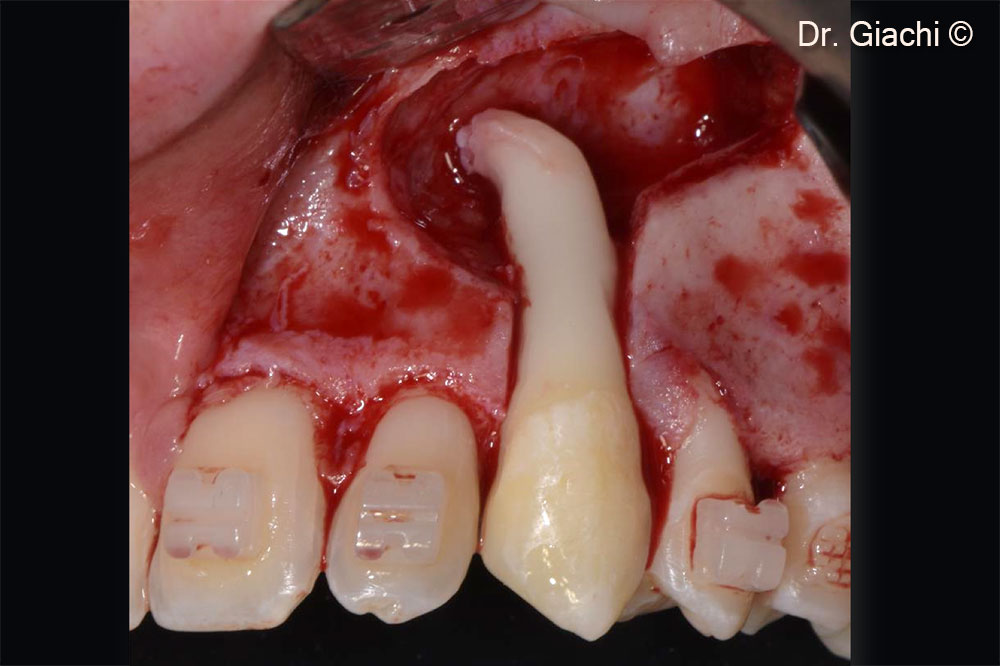

Một bệnh nhân nam (16 tuổi) có răng nanh trên không thể phục hồi bằng phương pháp chỉnh nha truyền thống.